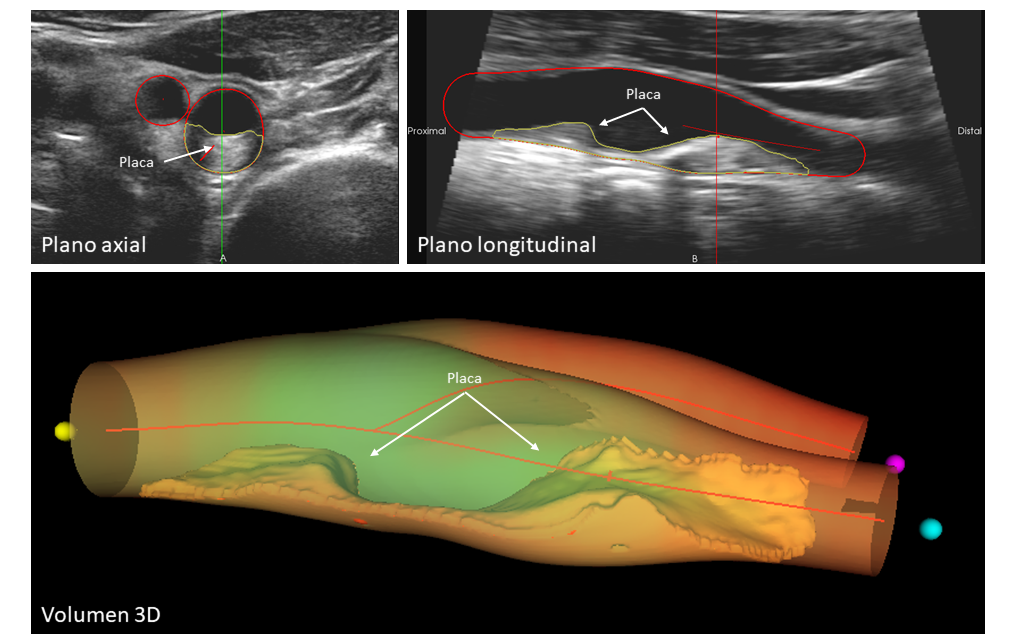

Sobre el CNIC 15 Mayo 2024 CNIC colidera REACT, un proyecto internacional de medicina de precisión para transformar la prevención cardiovascular. REACT tiene como objetivo combatir la aterosclerosis mediante la detección temprana y el tratamiento personalizado. Está previsto que REACT tenga una duración de 8 años divididos en dos fases con evaluación intermedia. Para la primera fase de 2.5 años, la financiación concedida por la Fundación Novo Nordisk es de 23 millones de euros |